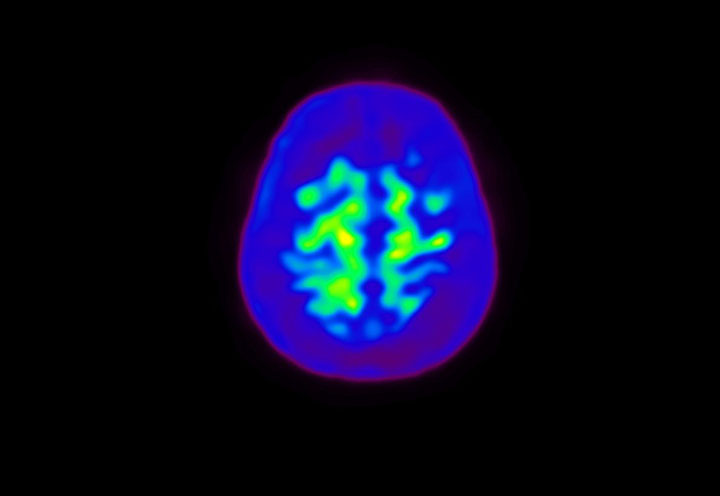

Head / Case4 : Amyloid

Axial

Courtesy : Kindai University Hospital

- Imaging protocol

- Injected dose: 3.21 MBq/kg, 18F-Flutemetamol

- Uptake time: 100 minutes

- Scan time: 20 minutes